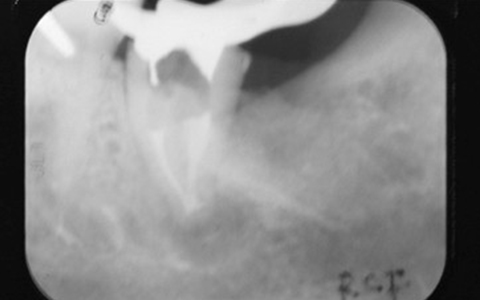

さらに再根管治療をしている歯のCTを撮影すると、歯根が破折していないにも関わらず、CTでは歯根が破折しているように見えることがあり、実は私達が見ているレントゲン(CTも含めて)は、その画像だけでは正しく診断できません。

通常のレントゲンは平面による撮影のため情報量少なく正確な診断が難しいですが、歯科用CTは三次元の立体的な画像で確認することができるため、神経の位置や根管内もしっかりと確認できます。

精密な治療をご提供するために、歯科用CTによる正確な画像診断を行うことがあります。